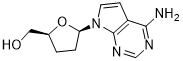

馬鞍山致研生物醫(yī)藥科技有限公司成立于馬鞍山市鄭浦港新區(qū)現(xiàn)代產(chǎn)業(yè)園。公司專(zhuān)注于生物小分子、醫(yī)藥中間體相關(guān)產(chǎn)品的研發(fā)和生產(chǎn),產(chǎn)品主要包括DNA亞磷酰胺單體、RNA亞磷酰胺單體、特殊單體以及按照客戶(hù)要求定制的RNA和DNA,并且公司提供定制合成等方面的研究服...

馬鞍山致研生物醫(yī)藥科技有限公司成立于馬鞍山市鄭浦港新區(qū)現(xiàn)代產(chǎn)業(yè)園。公司專(zhuān)注于生物小分子、醫(yī)藥中間體相關(guān)產(chǎn)品的研發(fā)和生產(chǎn),產(chǎn)品主要包括DNA亞磷酰胺單體、RNA亞磷酰胺單體、特殊單體以及按照客戶(hù)要求定制的RNA和DNA,并且公司提供定制合成等方面的研究服...